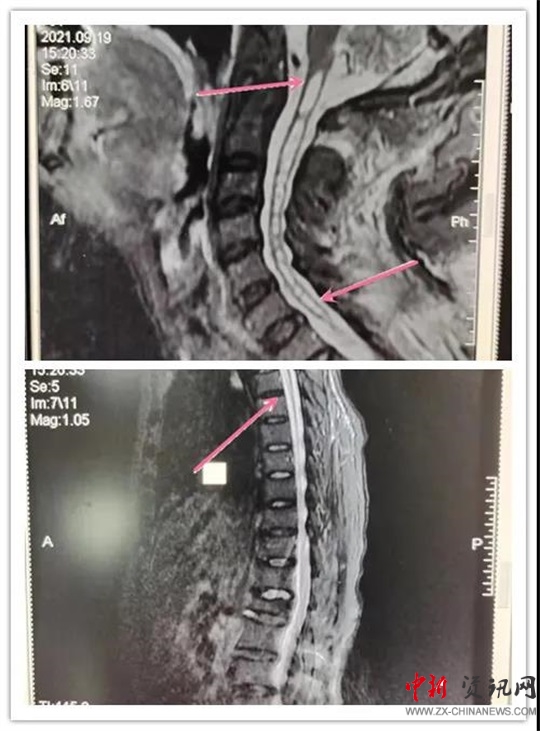

患者,女,70歲,六年前患脊髓空洞癥在某醫(yī)院行“脊髓空洞蛛網(wǎng)膜下腔分流手術(shù)”后病情好轉(zhuǎn)。近段時(shí)間,因“后肩部疼痛,無(wú)痛溫覺(jué)喪失,雙下肢疼痛、無(wú)力逐漸加重”癥狀加重,來(lái)汝南縣人民醫(yī)院就診,行MR檢查診斷為“頸胸脊髓空洞”。神經(jīng)外科副主任沈明輝認(rèn)真研究了患者的病情和 MR片子,認(rèn)為手術(shù)可行,隨即收住患者到科室;颊呷朐汉,完善了術(shù)前檢查,由于患者年事已高,患有高血壓、心臟病等疾病,使病情更加復(fù)雜,手術(shù)難度風(fēng)險(xiǎn)進(jìn)一步加大。手術(shù)團(tuán)隊(duì)組織了全科會(huì)診,對(duì)患者手術(shù)情怳進(jìn)行了分析。如果不做手術(shù),病情進(jìn)一步發(fā)展,患者雙下肢會(huì)截癱,再做手術(shù)也很難恢復(fù)。在得到患者家屬的理解和支持后,根據(jù)患者的病情,手術(shù)團(tuán)隊(duì)反復(fù)討論術(shù)中可能出現(xiàn)的問(wèn)題:完善圍手術(shù)期應(yīng)急預(yù)案,制定精準(zhǔn)的治療及手術(shù)方案,擇期為患者成功實(shí)施了“頸胸脊髓空洞胸腔引流”手術(shù)。術(shù)后患者雙下肢肌力明顯好轉(zhuǎn),正在康復(fù)中。

手術(shù)后